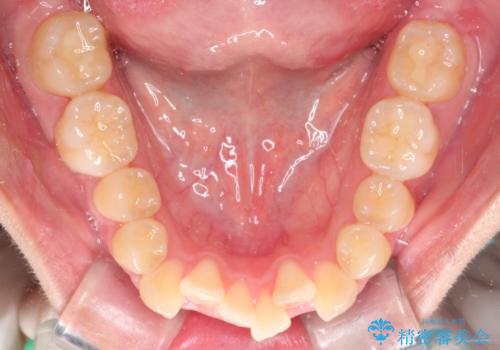

- 八重歯と口元が出ていることを主訴に来院されました。

レントゲンの検査において、前歯も外側に傾いてる結果であったため、上下左右の小臼歯を抜歯して配列を行いました。

歯の動きも良く短期間で治療を終えられたため患者さんにも大変満足していただきました。